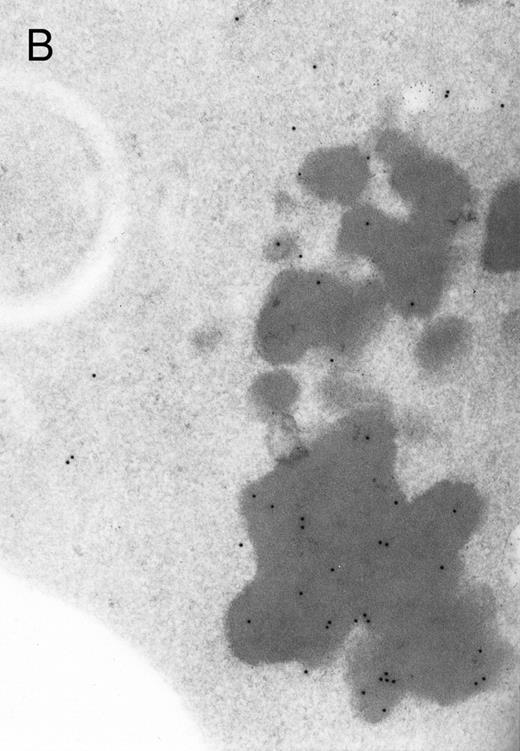

In both cases no. 1 and no. 2, electron microscope studies demonstrated electron-dense inclusions in 30% of early and late polychromatic erythroblast sections and many marrow reticulocytes. In ultrathin sections that reacted with monoclonal antibodies to either α- or β-globin chains followed by gold-labeled anti-mouse IgG, the density of gold particles over the majority of the inclusions was clearly greater than that over surrounding inclusion-free cytoplasm (Fig 3). By contrast, in sections from the two patients with β-thalassemia major, gold particles were concentrated over the inclusions following incubation with the antibody to α-globin chains, but not to β-globin chains (Fig 4A-C). The density of gold particles over inclusions in all control preparations was not greater than that over surrounding cytoplasm (Fig 4D).

Electron micrographs of erythroblastic inclusions from sections of marrow immunogold-labeled with mouse monoclonal antibody. Inclusions from case no. 1 show positive reactions with antibody against α-globin chains (A) and β-globin chains (B). Inclusions from case no. 2 show positive reactions with antibody against α-globin chains (C) and β-globin chains (D). Magnifications: A, × 32,000; B, × 38,000; C, × 32,000; D, × 37,000.